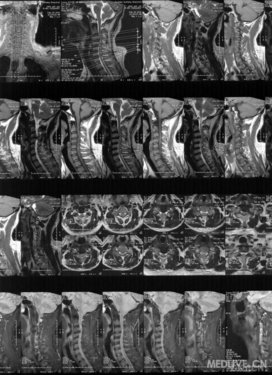

颈椎MRI

MRI提示:T2WI C2-7椎间盘信号减低,颈椎退行性改变。颈椎3/4椎间盘突出为重,局部高信号,脊髓前间隙变窄。